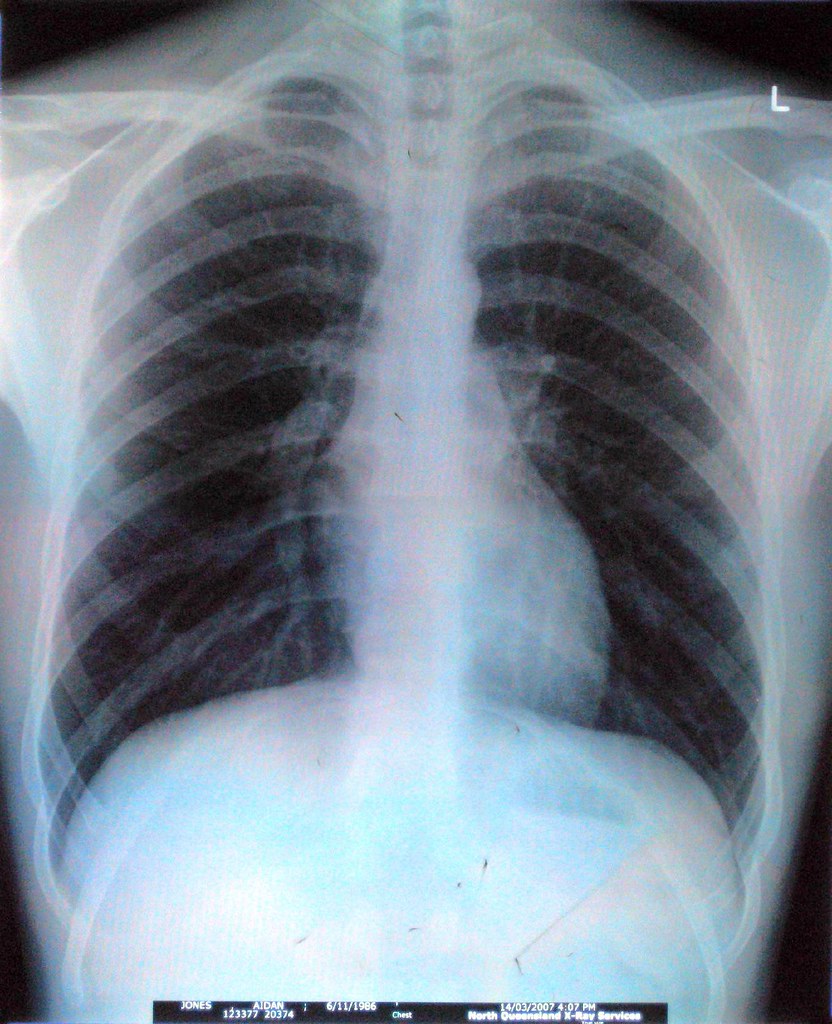

An artificial intelligence tool to interpret chest X-rays shows promise in Bengaluru trials Reading a chest X-ray is tough. So much so that even radiologists get it right only around 70-80% of the time. What if they got help from ‘machine eyes’?